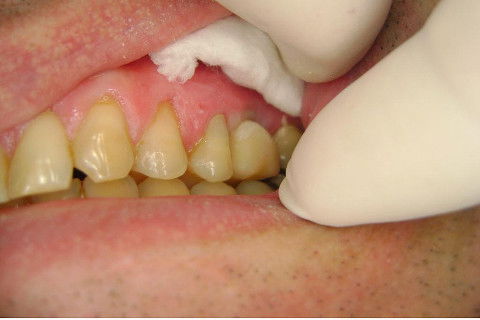

Instalação de um implante em região do 26. Utilizamos um implante cone morse Alvim Neodent 4.3 X 11,5. Foi uma cirurgia muito rápída e minimamente traumática, sem retalho e sutura.

Fotos do caso